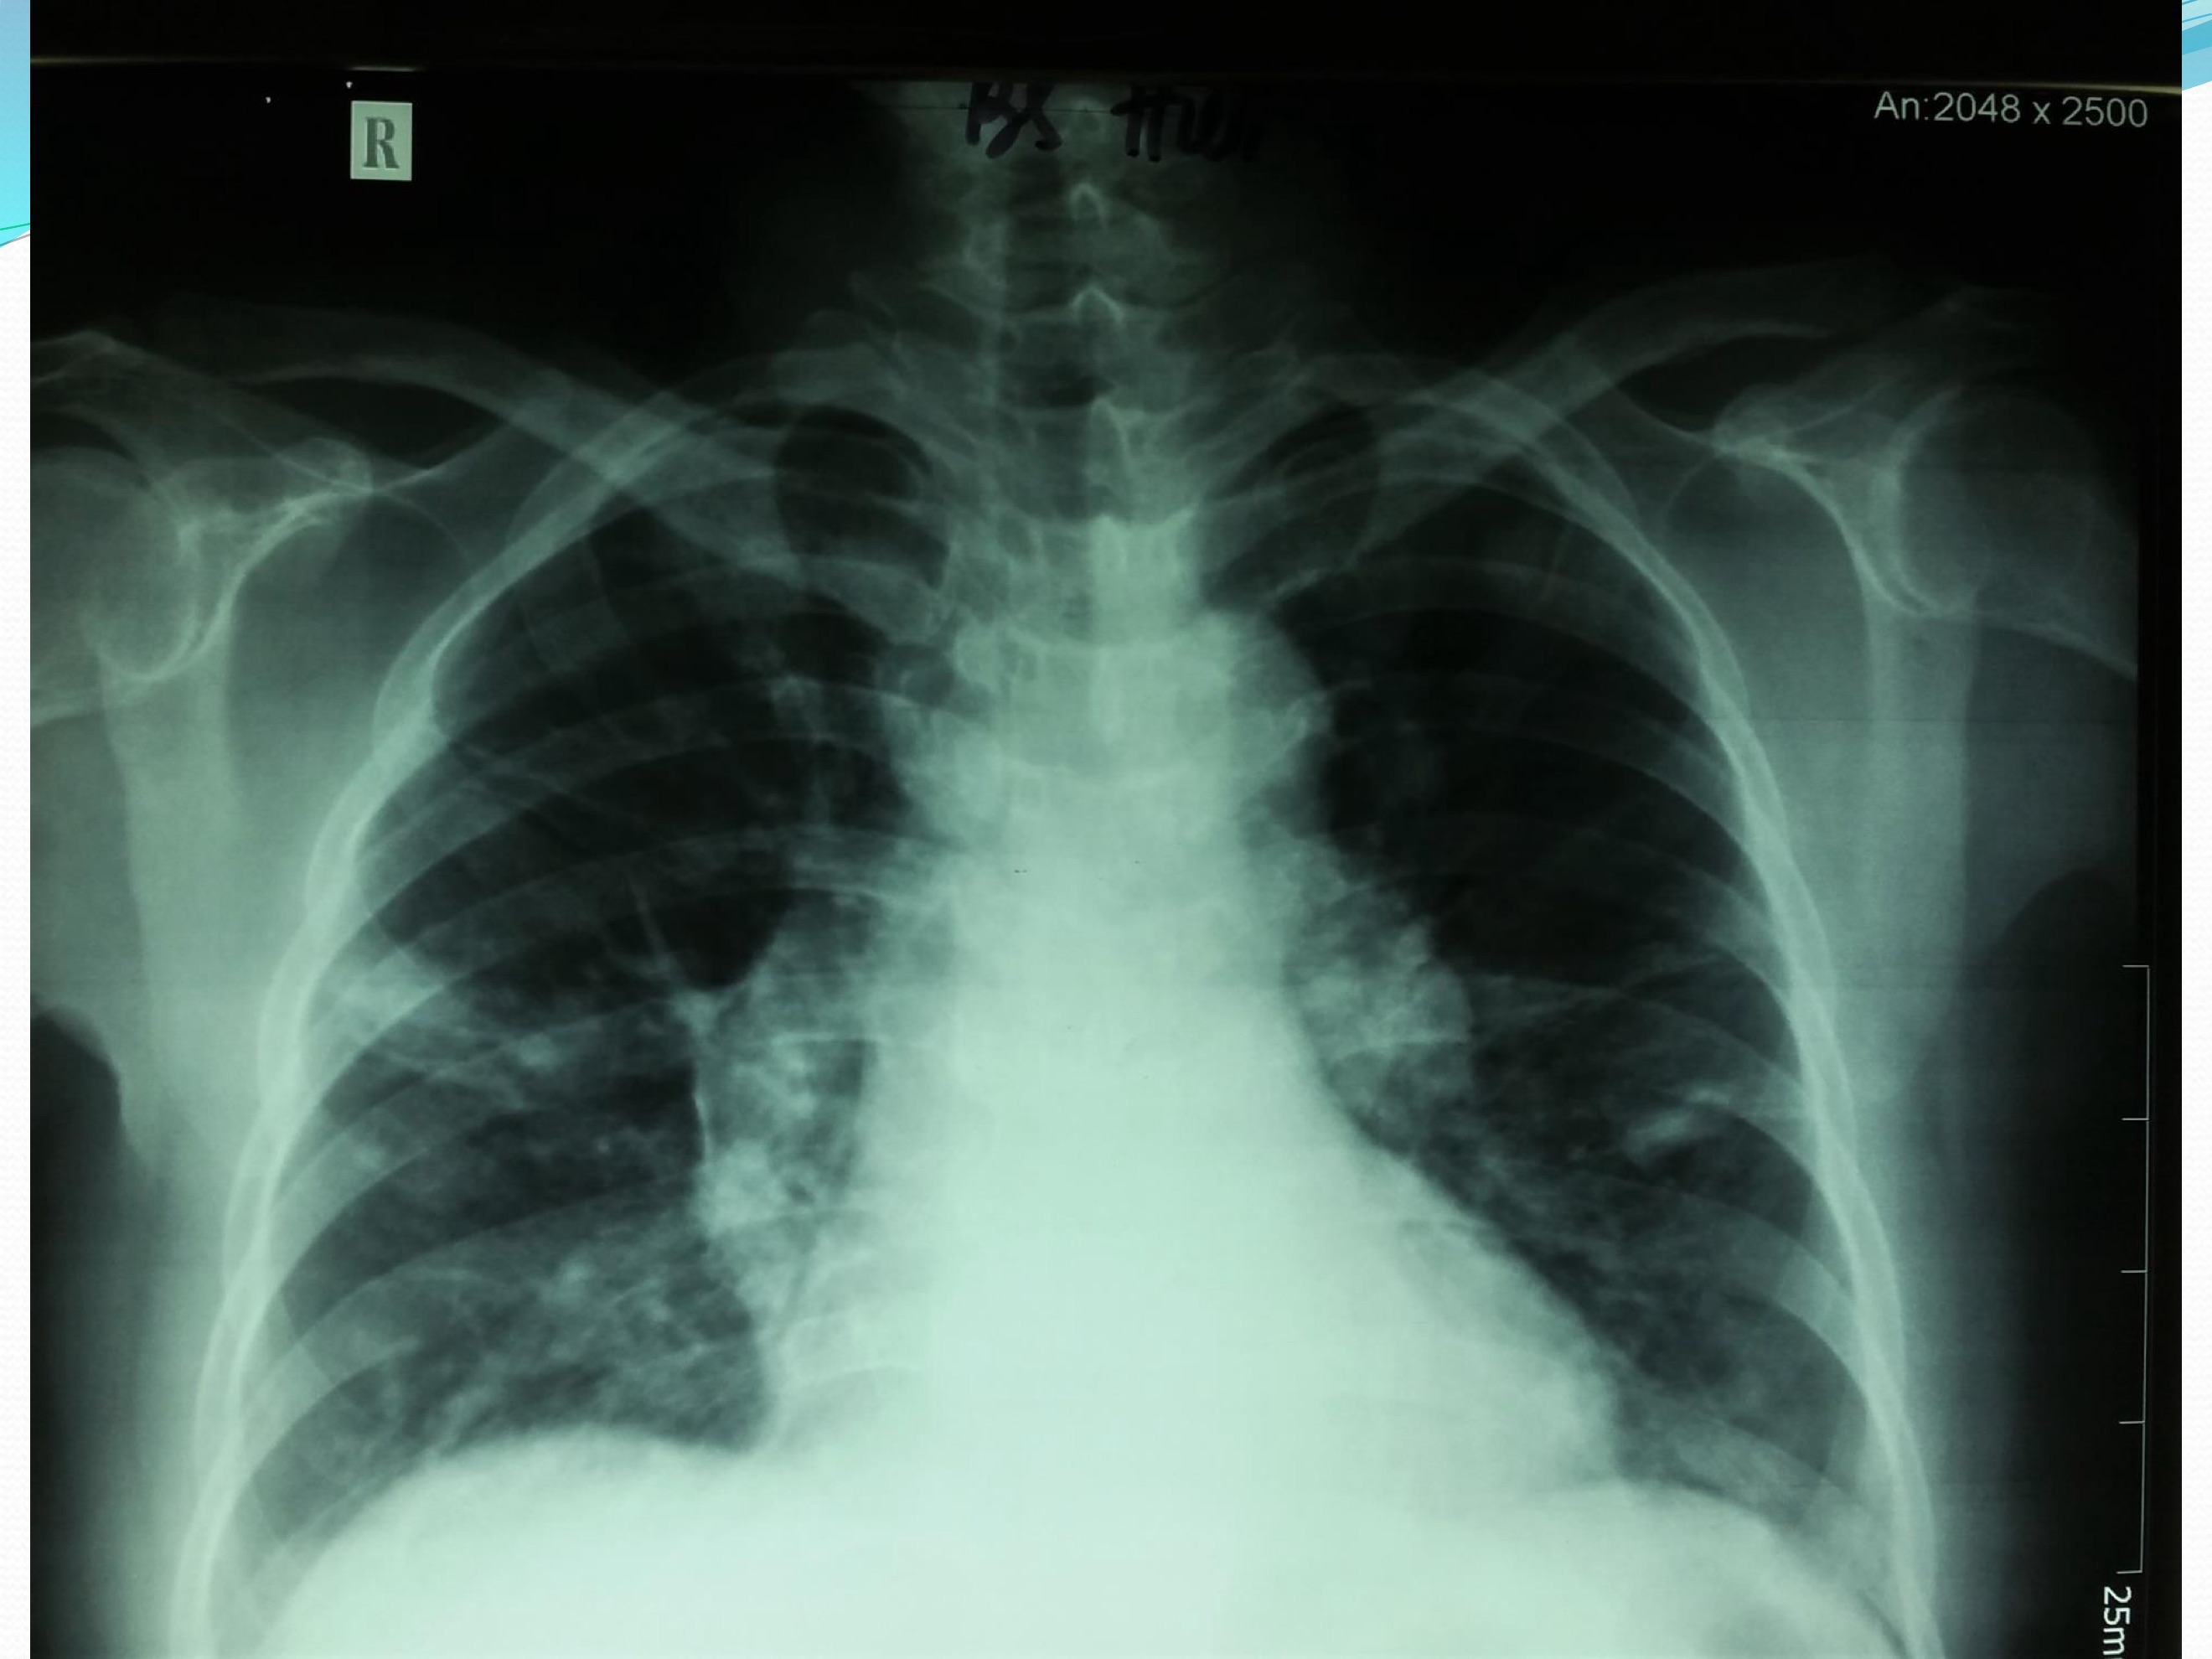

- X quang ngực thẳng: tổn thương đám mờ 2 phổi

- CT scan ngực: tổn thương phổi đa nốt 2 bên 0,5-1cm